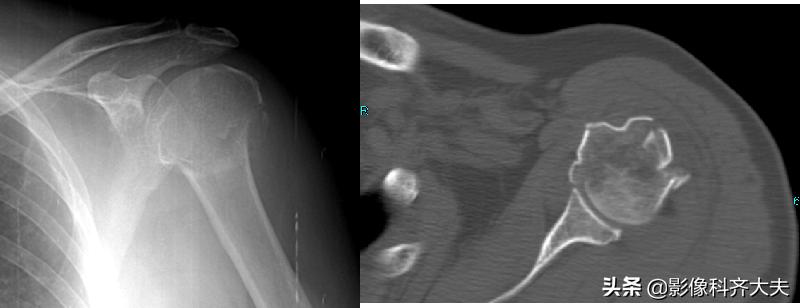

应用于解剖复杂部位

骨盆、髋、肩、膝、面骨、脊柱

了解有无骨折、骨折片的数目和位置

三位重建可立体显示骨折的详情